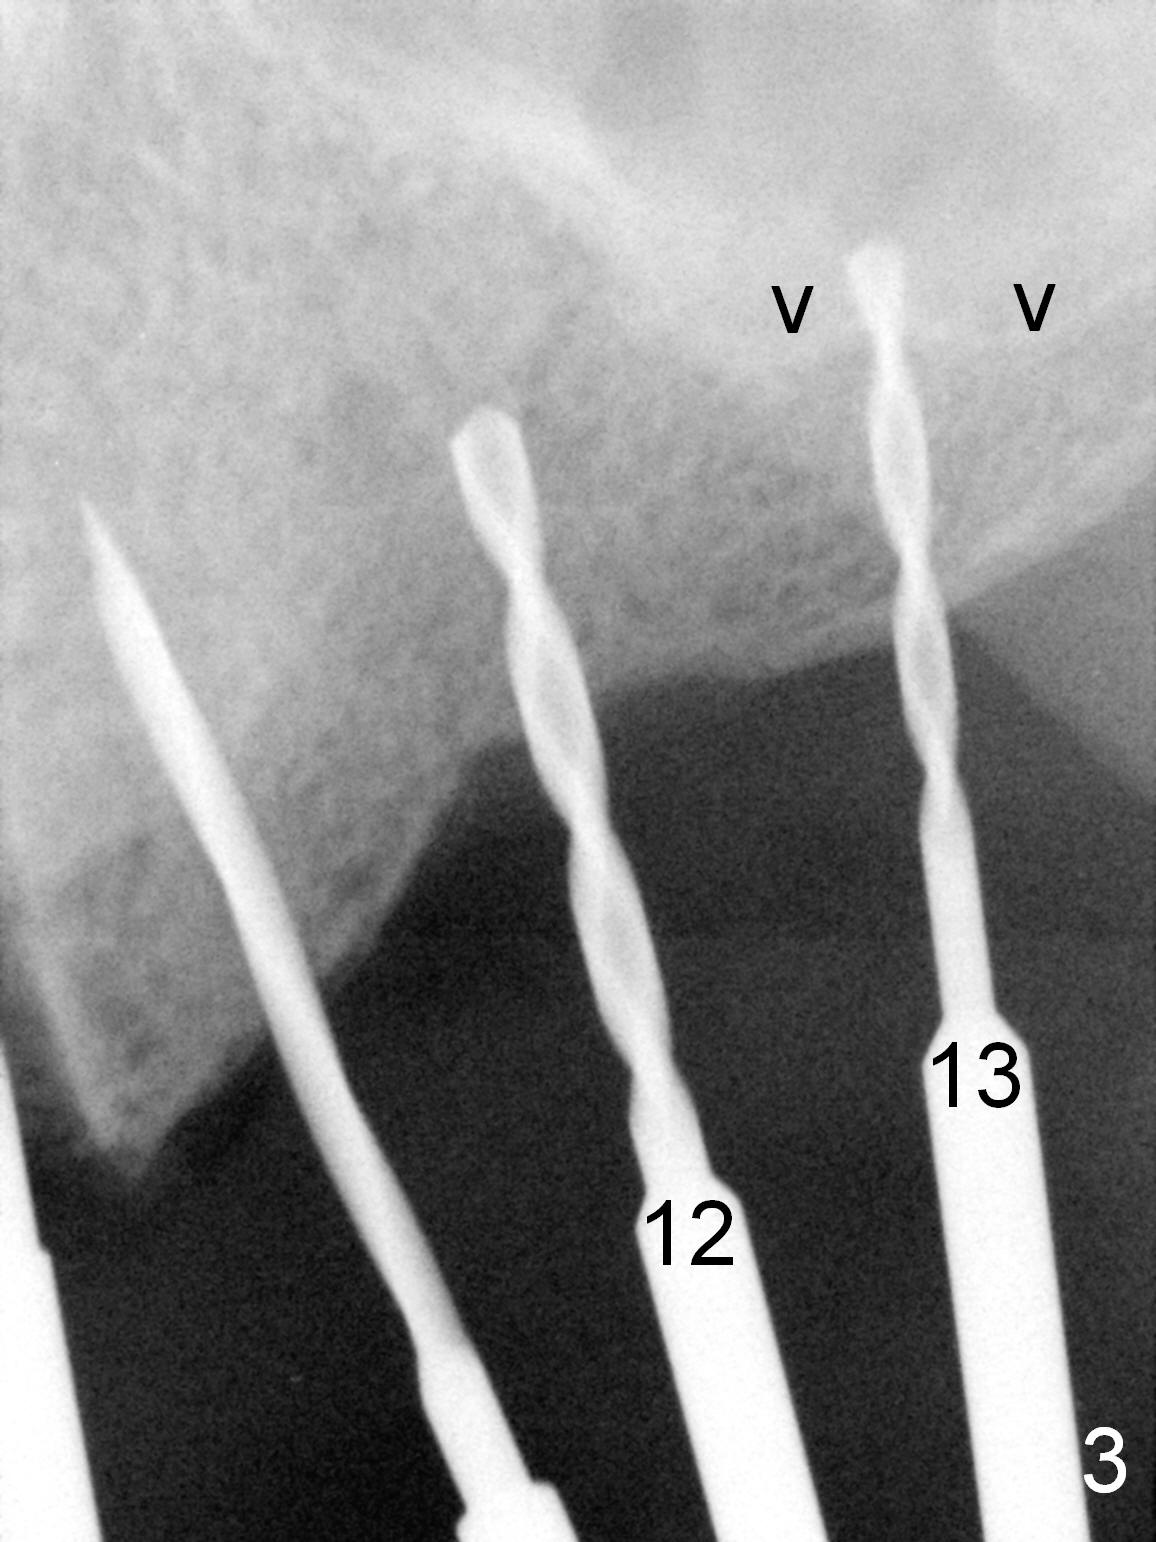

When the patient returns for implant placement (2nd visit after initial exam), he reveals that he is a dental phobic.  He requests placement of 4 implants in the upper left quadrant, instead of 2.  Narrow ridge is unexpected in the canine and premolar area (Fig.1).  Limited bone height at #13 (Fig.3 arrowheads: sinus floor) is found when initial drills are in place (Fig.2,3).  A 2-piece implant (4.5x17 mm tissue-level) is placed at #10 after extraction, while 1-piece implants are placed at 11 (3x17 mm (tissue-level, 15 °) and 12 and 13 (bone-level, 2.5x14, 12 mm, respectively; Fig.4,5).  In fact the 1 piece implant at #13 is not completely placed (Fig.5).  It is removed, the apical 3 threads are cut off (Fig.6 <, since a shorter implant was unavailable in the office) and the remaining implant is re-inserted.  The insertion torques of the 4 implants are ~ 60, ~ 35, < 35 and 15 Ncm, respectively.  After adjustment (Fig.7), immediate provisionals are fabricated at #10 and 11 (Fig.8, later splinted with composite), while perio dressing is applied around the implants at #12 and 13 and the provisionals at #10 and 11.  There is no nasal hemorrhage postop.  Although the perio dressing is loose 1 week postop (Fig.9), it is not removed.  When the upper lip fissure (Fig.9 <) heals, provisionals at #12 and 13 are planned to be splinted to the other two ones.  Two weeks postop, the upper lip fissure heals, the perio dressing dislodges and the implants at #12 and 13 are stable (Fig.10).  After abutment height adjustment, a splinted provisional is fabricated over these 2.5 mm 1-piece implants (Fig.11).